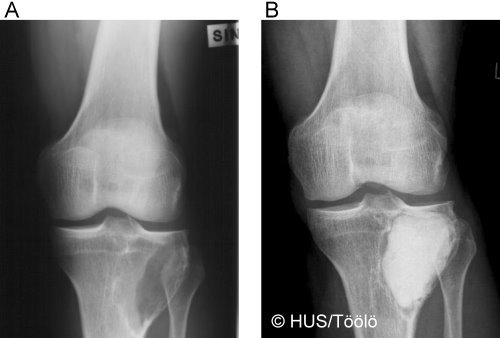

Giant Cell Tumour of Tibia

Giant cell tumour of tibia. A. Giant cell tumour of tibia. B. Giant cell tumour after bone cement filling.

Picture: Aarne Kivioja / HUCH/Töölö Hospital